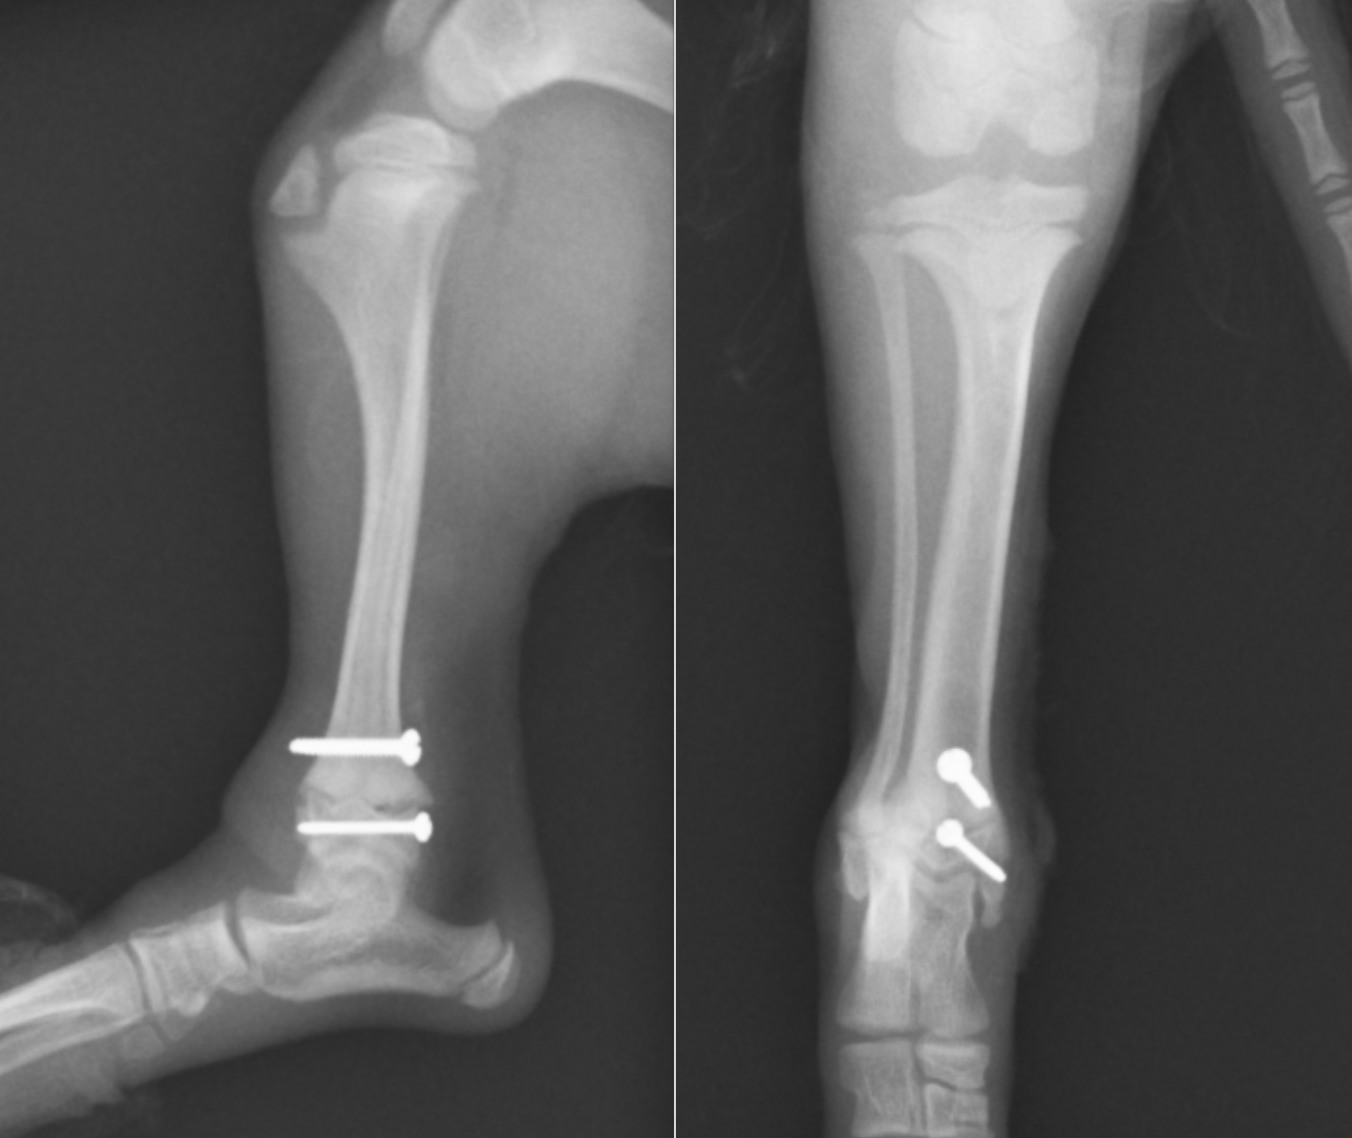

手術ではスクリュー2本を使用し、ラグスクリュー法という方法で圧迫固定しています。術前にあった亀裂がピタッと固定されているのがわかるかと思います。

術後次の日には元気に4本足で歩行可能となり、5日で退院し通常通りの生活を送っています。術後1ヶ月ほどでスクリューを抜去し終了となります。